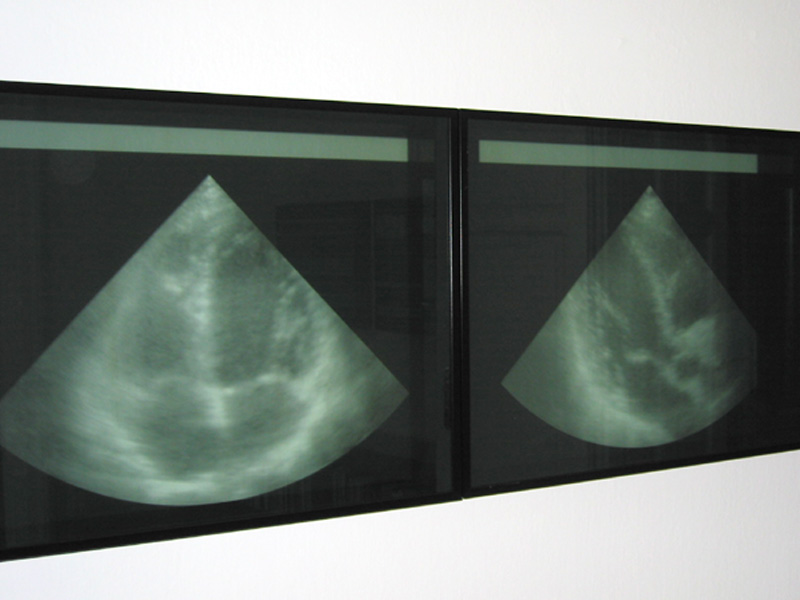

Wandinstallation/Teilansicht

Melitta Moschik HUMAN INTERFACE 2001

4 teilige Wandinstallation, 320 x 60 cm

Sono-/Computergrafische Filme in schwarzen Alu- Kasten